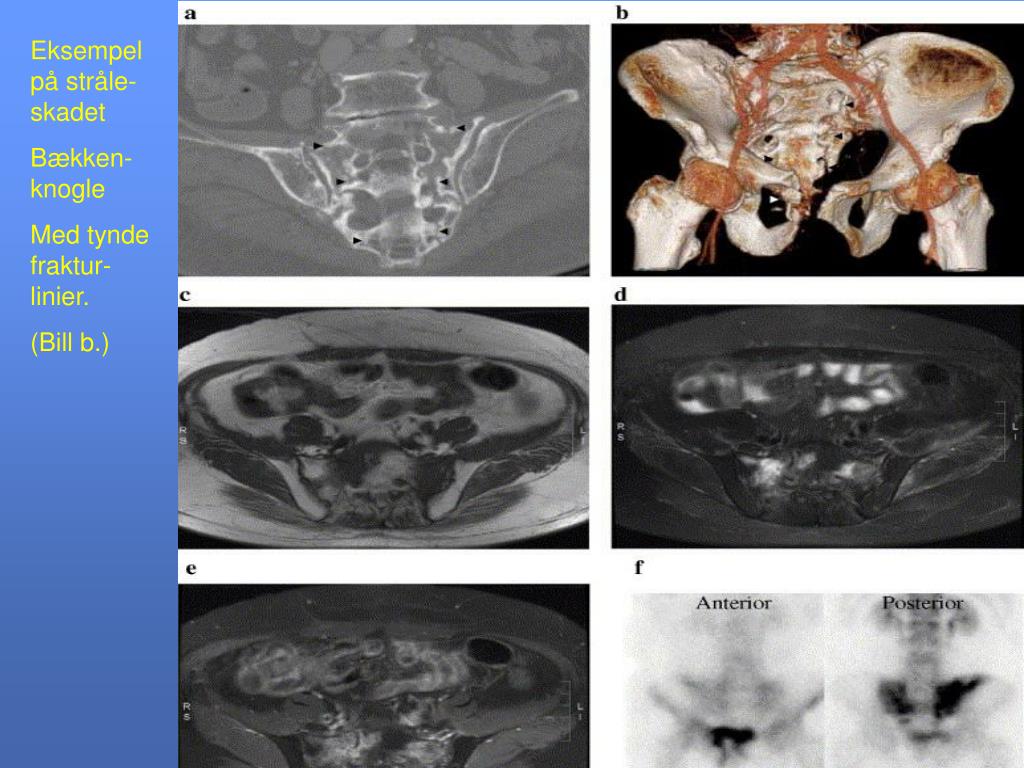

18. Eksempel på stråle-skadet Bækken-knogle Med tynde fraktur-linier. (Bill b.)